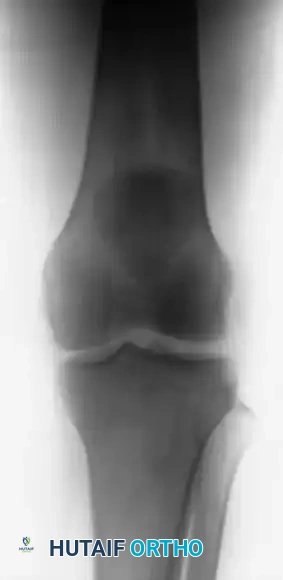

Radiographic Evaluation:

Standard anteroposterior (AP) and lateral radiographs are mandatory. A lateral radiograph, particularly with the knee flexed to 30 degrees, is highly sensitive for evaluating patellar height. A superiorly displaced patella (Insall-Salvati ratio > 1.2) confirms a patellar tendon rupture. If the clinical diagnosis remains equivocal due to swelling or patient guarding, ultrasonography or Magnetic Resonance Imaging (MRI) provides definitive visualization of the soft tissue defect.

FIGURE 48-30: Anteroposterior and lateral radiographs demonstrating an acute patellar tendon rupture. Note the significant superior displacement of the patella (patella alta) on the lateral view, caused by the unopposed contraction of the quadriceps muscle.